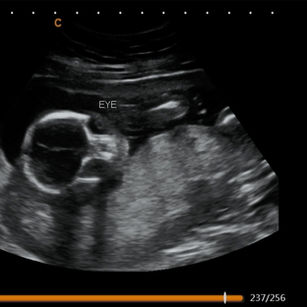

18 Weeks Pregnant

Size: ~5.5 inches (14 cm), the size of a Bell Pepper!

Development Highlights:

Baby can hear sounds and may respond.

Vernix caseosa begins forming to protect skin.

Joints more flexible; baby can bend arms and legs.

Baby may start thumb sucking.